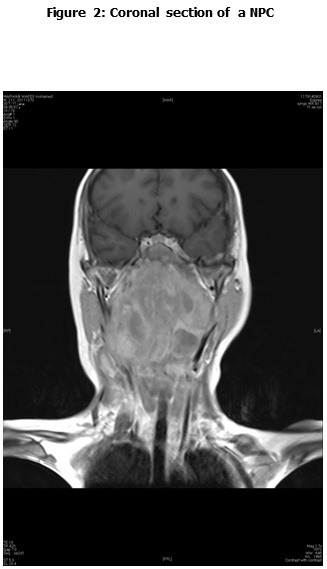

This is a retrospective study including all the newly diagnosed pediatric NPC who were diagnosed and treated at the Children Cancer Hospital Egypt (CCHE) during the period from July 2007 to December 2012. All imaging studies (e.g., CT or MRI scans) were reviewed by a senior head and neck radiologist for proper staging and assessment of tumor response. Patients were staged according to AJCC staging system. Modified version of the Response Evaluation Criteria in Solid Tumor (RECIST) was used to assess response.

This is a retrospective study including all newly diagnosed pediatric NPC at Children Cancer Hospital Egypt CCHE during the time period from July 2007 to December 2012. The patients' profiles were systematically reviewed for characteristics including pathology, laboratory, radiological work up and documented toxicities. All imaging studies (e.g., CT and MRI scans) were reviewed by a senior head and neck radiologist for proper staging and assessment of tumor response.

Pretreatment evaluation included a complete history and physical examination, complete blood count, serum biochemistry tests (including evaluation of electrolyte levels, hepatic and renal function tests), CT or MRI scans of the head and neck region, chest and bone scan. During therapy weekly examinations and laboratory evaluations were performed. Tumor response was assessed by clinical examination with appropriate MRI imaging studies after completion of neoadjuvant chemotherapy and at the end of radiotherapy.

The most common presentation was dysphagia seen in 23 patients (88.5%), followed by cervical lymphadenopathy in 21 (80.8%), and symptoms of increased intracranial pressure in 19 (73%) patients. The T1, T2, T3 and T4 tumor size was presented in 2 (7.7%), 5 (19.2%), 8 (30.8%) and 11 (42.3%) patients respectively. N0, N1, N2 and N3 was detected in 1 (2.8%), 8 (30.8%), 16 (61.5%) and 1 (3.8%) patients respectively. Three patients (11.5%) were metastatic at presentation.